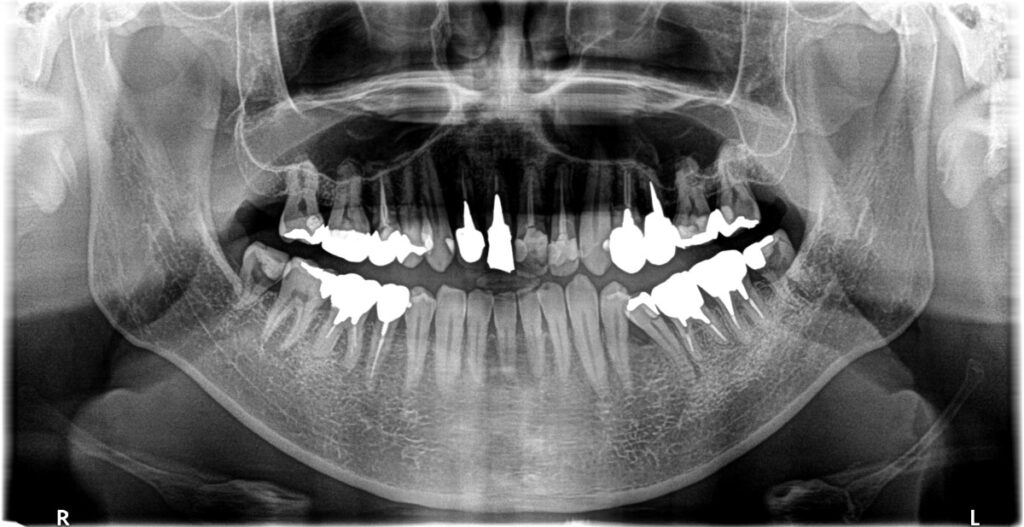

- 初診:2019年、40代男性、非喫煙者、アレルギー体質(花粉症)

- 矯正診断:3級骨格性の反対咬合

治療期間は約3年でした。本来、外科矯正も視野にいれた方が良いかもしれない、ウルトラE難度のケースだったと思います。しかし年齢的な問題、歯の問題も解決しないといけないため、歯並びは治っても骨格的な問題は解決できないと患者さんに最初に説明してから治療に入りました。しかし、本人最終的な仕上がりには大変満足しているようです。

更に化膿していた歯根も全て当医院の再治療で完治したことがCT画像でもわかるため、大変感謝されました。ただ、本来アレルギー体質も考慮して、全てメタルフリーという考えもありましたが、問題ない銀歯を触り神経の処置が必要になるリスクも考慮して、そのまま経過観察とさせて頂きました。また、咬合負担のかかり側方圧のかかりやすい親知らずの修復にはゴールド修復を行いました。いずれ皮膚科に金属アレルギーの検査に行ってもらい、陽性反応がでればやり直す予定ですが、再修復に関しましては自費料金を割り引こうと考えています。